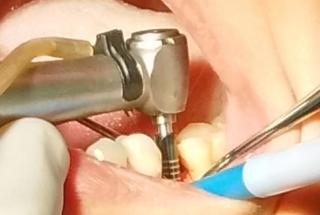

Clinical cases

MPI closely monitors clinical cases in the market to ensure their correct functioning and successful outcome.